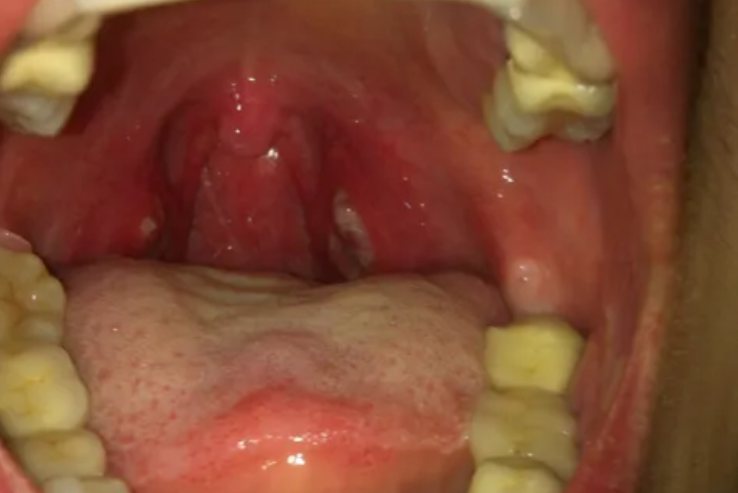

2、扁桃体周围脓肿

扁桃体周围脓肿表现为扁桃体包膜、咽上缩肌与腭咽肌之间明确的积脓,也可在扁桃体周围间隙中存在多个积脓小腔。体查可见悬雍垂偏斜,扁桃体周围饱满或隆起,触之有波动感。患者自觉剧烈咽痛,伴张口困难。